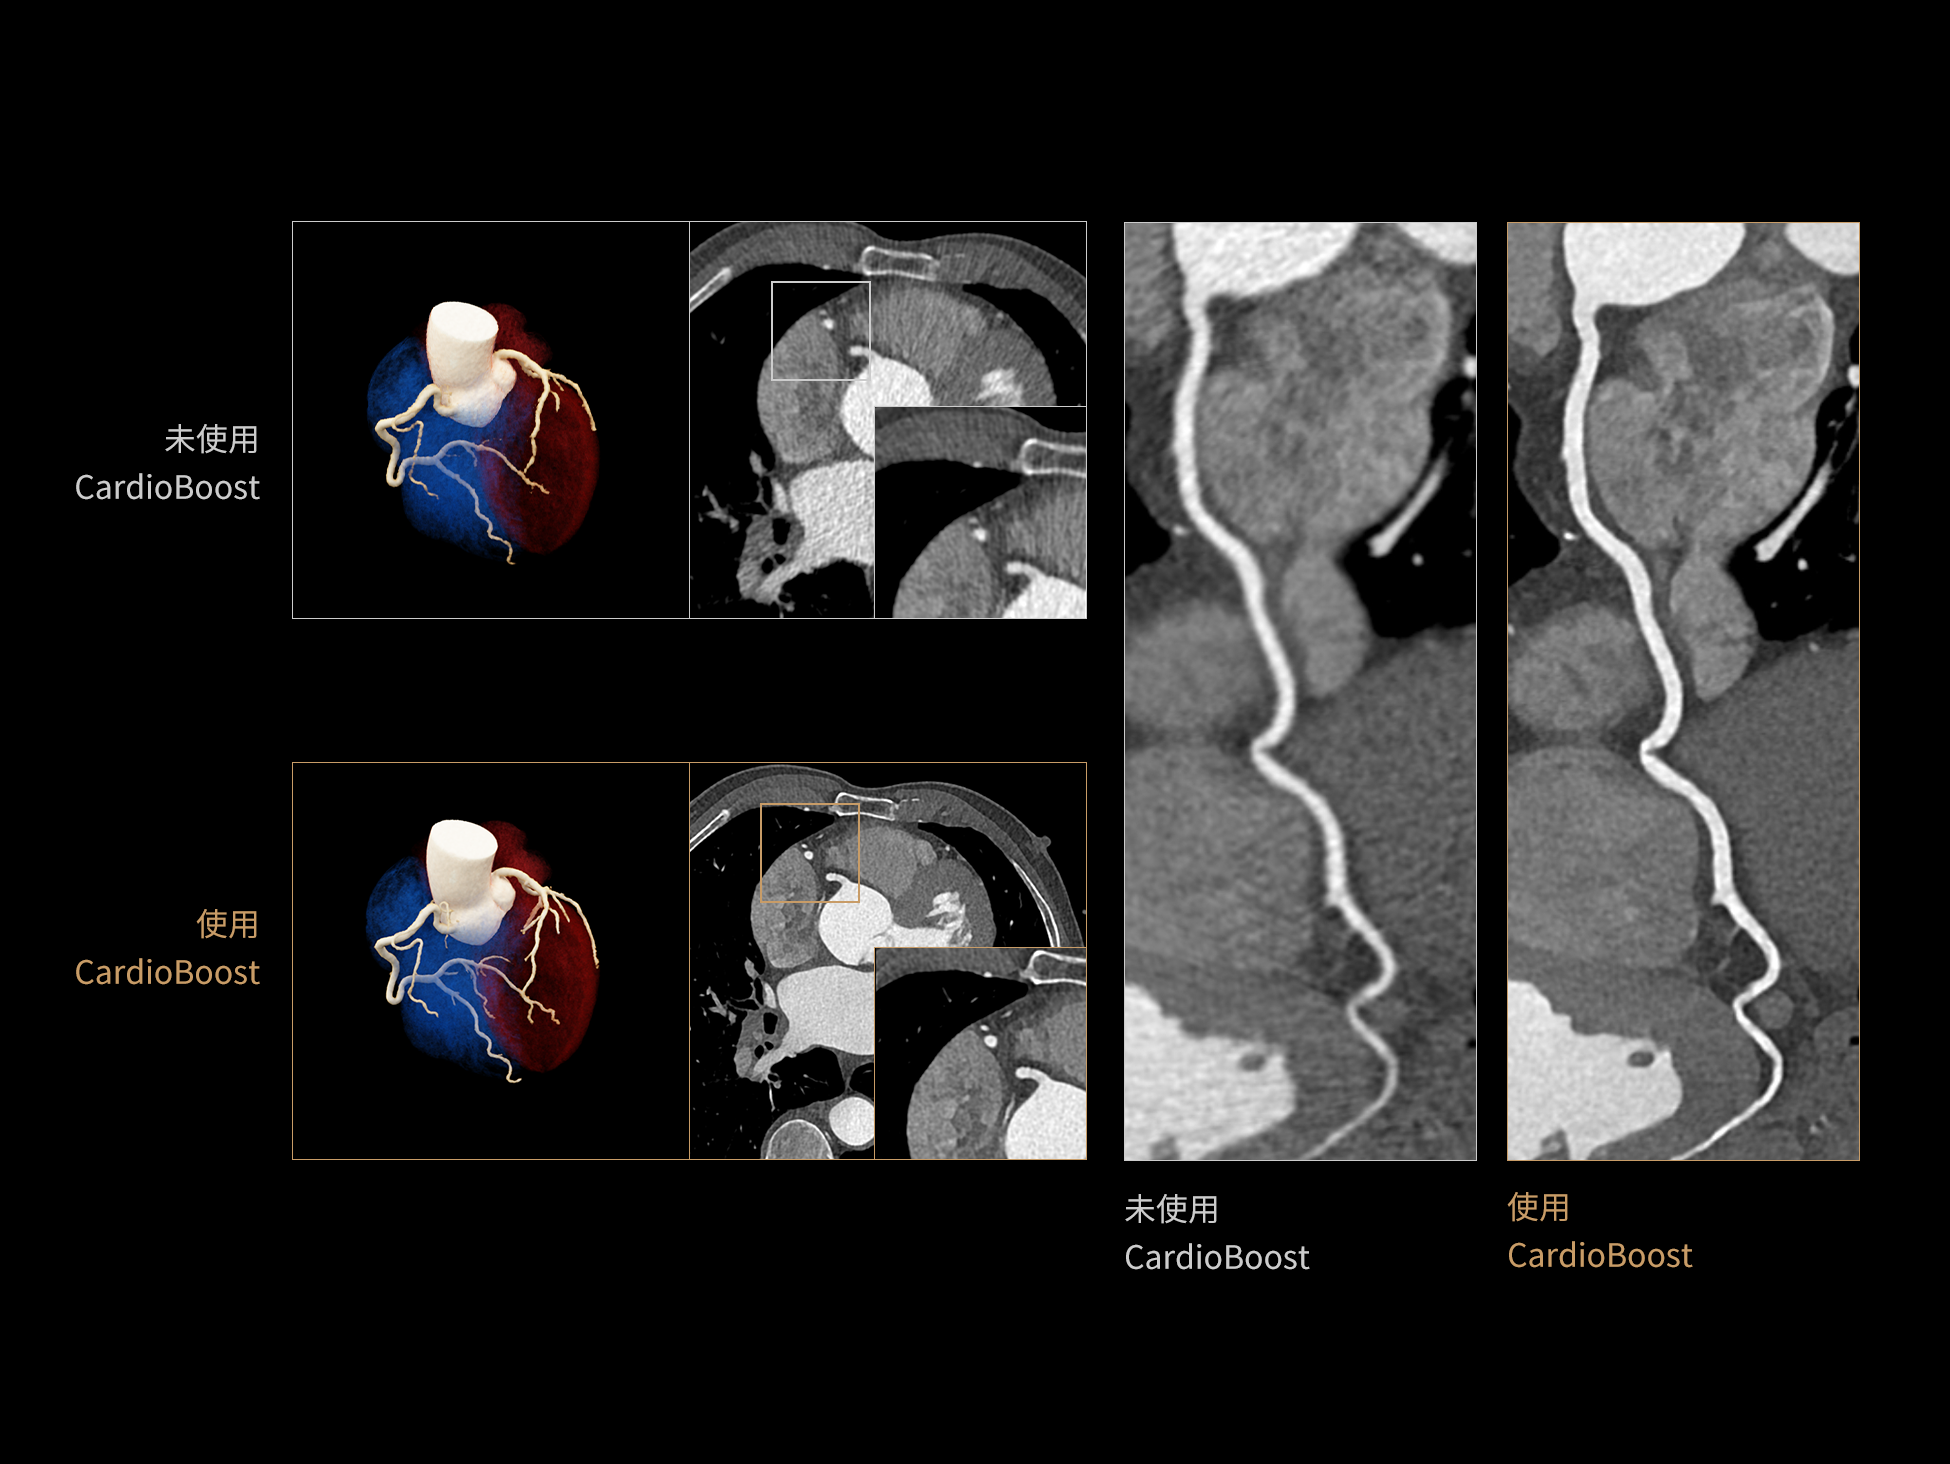

CardioBoost:专属网络设计,重塑心脏影像表现

目前心脏的 CT 检查还存在辐射剂量偏高、空间分辨率不足、 致密钙化伪影影响冠脉狭窄程度评估等方面的限 制[1][2]。CardioBoost 技术专为心脏 CT 高清成像而开发,通过 3D 神经网络的深度学习技术,利用先进的注意力机制在识别关键成像特征方面的出色表现,能够精确地聚焦于斑块、支架以及微小血管等关键细节,清晰展示这些结构与冠脉血管的边界,从而显著提高诊断的准确性,并提升医生的诊断信心。创新的 CardioBoost 心脏图像重建算法,不仅实现了图像清晰度的提升和伪影的去除,更能在减少辐射剂量的同时,保证心脏图像的高质量和图像纹理的自然。

采用 3D 神经网络的空间结构优势与精细的组织分类能力,CardioBoost 技术优化了组织对比,高清展示血管斑块,使斑块与血管边缘的轮廓清晰可辨,提升斑块诊断与评估的精确性。

借助 3D 神经网络设计、空间注意力机制聚焦与特征强化作用,CardioBoost技术提升图像的空间分辨率,实现冠脉支架的高清成像,对支架形态与管腔通畅度的评估更精准。

CardioBoost 整合先进的 3D 神经网络和空间注意力机制,大幅增强数据处理的速度与精确度。该技术能有效抑制由致密钙化引起的晕状伪影,清晰展现钙化斑块的原始结构和大小,对冠脉狭窄的评估更加精确可靠。